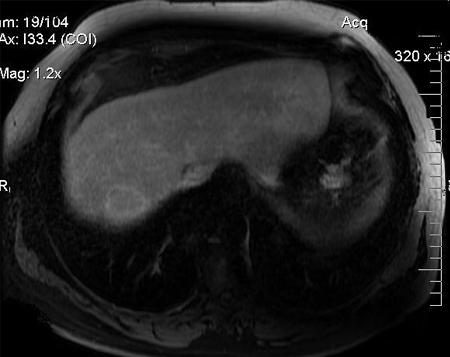

contrast MRI of abdomen

Test

If there is elevated alpha fetoprotein and/or abnormal ultrasound with focal liver lesion(s), then multiphasic CT or dynamic contrast-enhanced MRI of the abdomen should be ordered to confirm the diagnosis of hepatocellular carcinoma (HCC).[2][7][69]

The National Comprehensive Cancer Network (NCCN) suggests dynamic contrast-enhanced MRI (or CT) as an alternative to ultrasound for screening and surveillance if ultrasound is unable to detect nodules or if visualisation is poor.[2] The sensitivity of MRI of the abdomen for diagnosing HCC is 81%; specificity is 85%.[65]

MRI is superior to CT scan of the abdomen in differentiating dysplastic nodules, vascular lesions (haemangioma), and focal fat from HCC. However, one Cochrane review found that MRI may miss up to 16% of people with HCC, and 6% of patients without HCC may be treated unnecessarily.[71]

MRI is usually less readily available than CT, and the choice between the two modalities is typically centre-dependent.

Non-invasive diagnosis of HCC should be based on the Liver Imaging Reporting and Data System (LI-RADS) criteria.[2][62] ACR: Liver Imaging Reporting and Data System (LI-RADS®) Opens in new window

[Figure caption and citation for the preceding image starts]: MRI: washout portal phaseFrom the personal collection of Badar Muneer MD, Florida Hospital Transplant Center, Orlando, FL; used with permission [Citation ends].